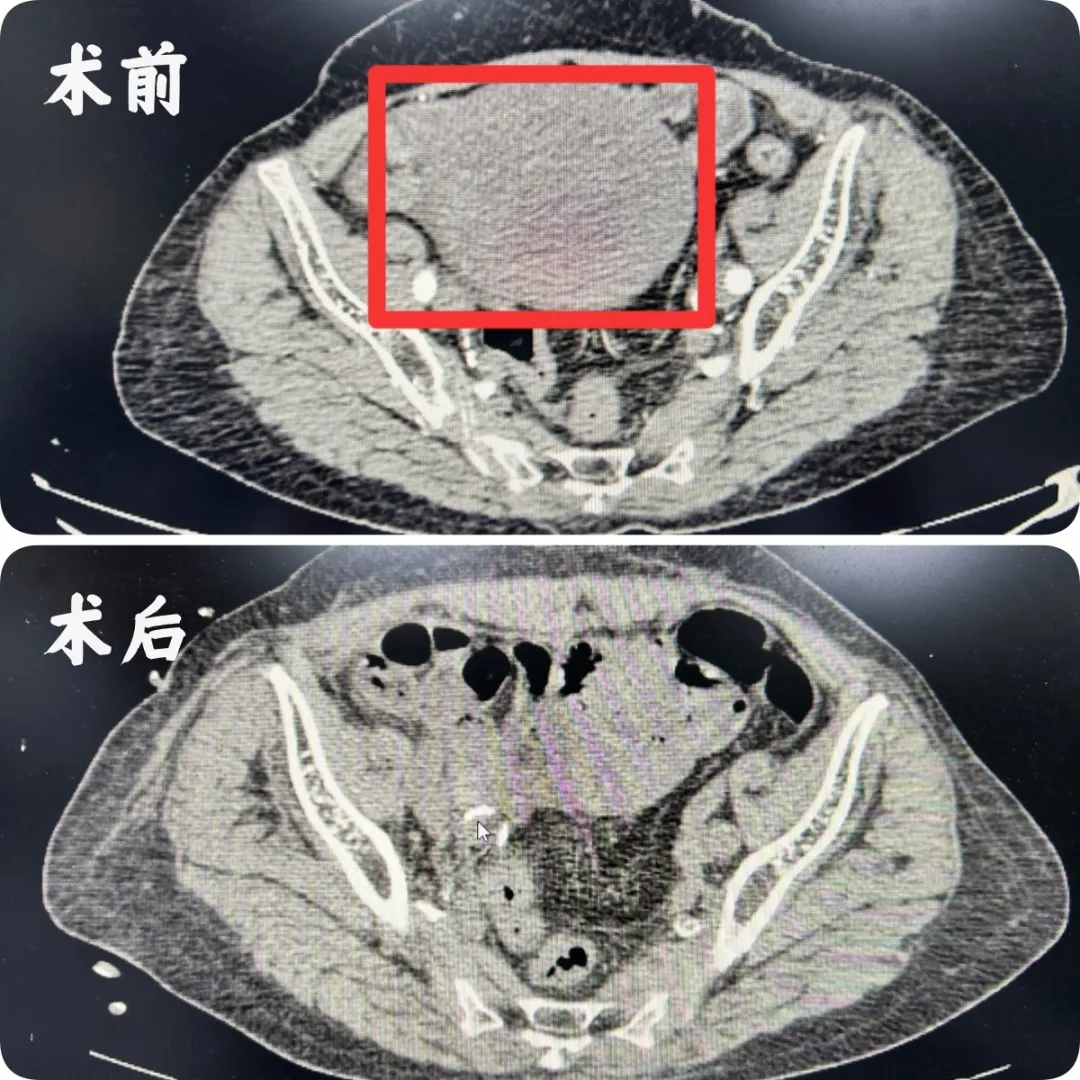

患者曹婆婆因持续下腹部胀痛来院就诊,经检查发现一直径约12厘米的球形肿瘤,已占据下腹腔及盆腔。肿瘤体积庞大且位置特殊,手术难度和风险系数高。

10月21日,在充分准备后,由郭恺主任主刀,陈杰、鄢传奇主治医师密切配合,手术紧张展开。术中,团队在腹腔镜高清视野下精准操作,细致分离肿瘤与周围组织的紧密粘连,完整切除巨大肿瘤并行右侧附件切除术。整台手术出血少、操作精准,展现了团队娴熟的腹腔镜技术和丰富的临床经验。术后,在医护团队的精心照护下,曹婆婆恢复迅速,腹胀症状完全缓解,术后次日即可下床活动,目前已康复出院。